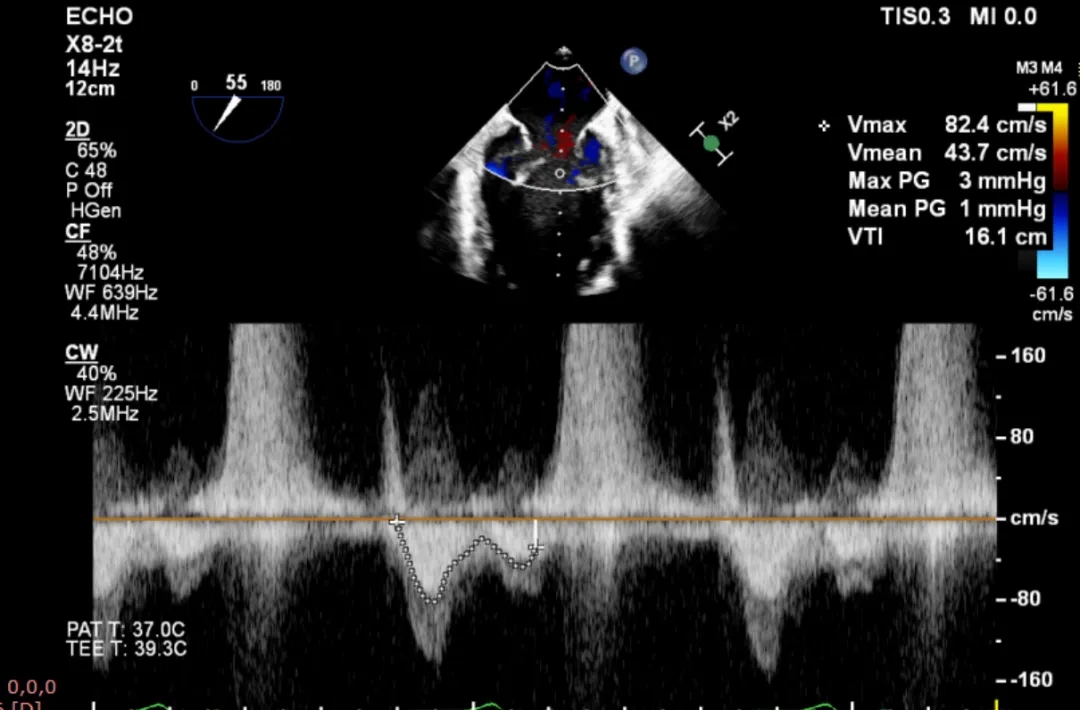

该例患者为VFMR,病变位于2区,病变解剖结构相对简单。术前制定手术策略:使用1把XTR解决患者二尖瓣反流。术中进行房间隔穿刺后将XTR-CDS送入左心房,通过操控“M”旋钮,成功将二尖瓣夹定位于2区正上方。在2区进行弹道测试成功后,进行Orientation调整。在2区将二尖瓣夹送入左心室,成功捕捞和夹持瓣叶后缓慢关紧夹臂。TEE检查见二尖瓣反流程度充分降低至1,二尖瓣双孔组织桥稳定,跨瓣压差1mmHg,肺静脉逆流改善明显,手术安全结束。

术后平均跨瓣压差1mmHg

该例患者为VFMR,病变位于2区,反流为中心性反流。术前制定手术策略:使用1把XTR解决患者二尖瓣反流。术中首先进行房间隔穿刺,最终穿刺高度4.2cm。穿刺成功后将SGC和XTR-CDS依次送入左心房,通过操控“M”旋钮调节SGC,使二尖瓣夹避开华法林脊并成功定位于2区正上方。在2区进行弹道测试成功后,进行Orientation调整。最终在2区将二尖瓣夹送入左心室,成功捕捞和夹持瓣叶后缓慢关紧夹臂。TEE检查见二尖瓣反流程度降低至微量,二尖瓣双孔组织桥稳定,跨瓣压差1mmHg,肺静脉逆流改善明显,手术安全结束。